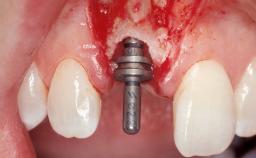

Late Flapless Placement of an Implant in a Maxillary Left Central Incisor Site

Type of Implants One-Piece

Placement Protocol Early or late implant placement

Bone Volume Deficient horizontally, requiring prior grafting

Loading Protocol Conventional or early